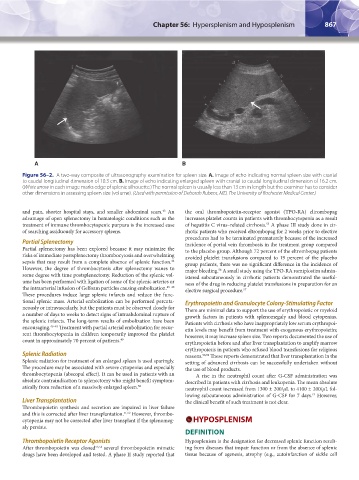

Figure 56–2. A two-way composite of ultrasonography examination for spleen size. A. Image of echo indicating normal spleen size with cranial

to caudal longitudinal dimension of 10.3 cm. B. Image of echo indicating enlarged spleen with cranial to caudal longitudinal dimension of 16.2 cm.

(White arrow in each image marks edge of splenic silhouette.) The normal spleen is usually less than 13 cm in length but the examiner has to consider

other dimensions in assessing spleen size (volume). (Used with permission of Deborah Rubens, MD, The University of Rochester Medical Center.)